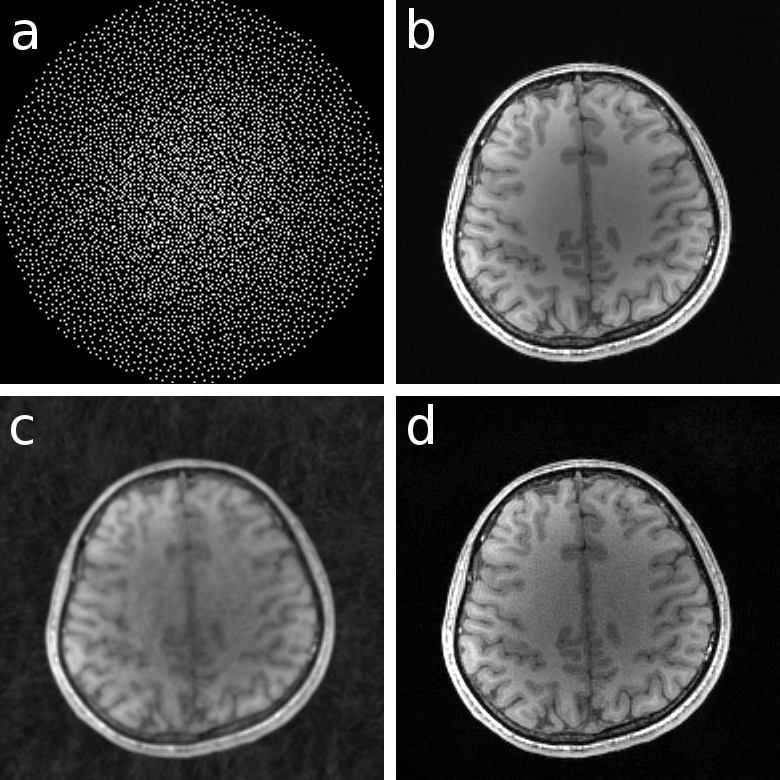

Here, is the sampling trajectory in the Fourier domain (k-space), and is a compactly supported region inside for two-dimensional or for three-dimensional imaging experiments. The extend of (field-of-view) in the image domain defines the bandwidth of the signal in k-space. If k-space is sampled according to the corresponding Nyquist rate it is referred to as fully sampled. As the signal equation is valid only for short durations, the acquisition of all required k-space samples has to be split into a repeated series of individual measurements, which makes the measurement process very time consuming. The main objective in parallel MRI is to reconstruct diagnostic images while reducing the number of samples as much as possible. Fig. 1 shows various common sampling schemes and Fig. 2 shows individual coil images and sensitivities for a modern 32-channel receiver-coil array.

Here, a weighting matrix that penalizes high Fourier coefficients to exploit the fact that sensitivities are smooth functions. Fig. 3 shows an experimental example. Inspired by ESPIRiT, this algorithm can be extended to multiple images and sets of sensitivities [12]: